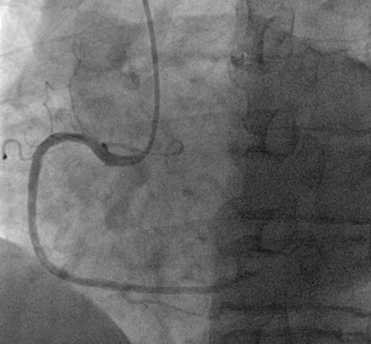

Los hallazgos fueron los siguientes:

· Tronco coronario izquierdo sin lesiones angiográficas significativas; descendente anterior (DA) estenosis severa entre tercio proximal y medio, suboclusiva; estenosis tercio distal coronaría derecha sin lesiones angiográficas significativas. (Ilustración 3 y 4).

Ilustración 3 Arteriografía coronaria derecha

Fuente: Hospital de Especialidades Guayaquil “Doctor Abel Gilbert Pontón”.

Ilustración 4 Arteriografía coronaria izquierda, lesiones en arteria descendente anterior